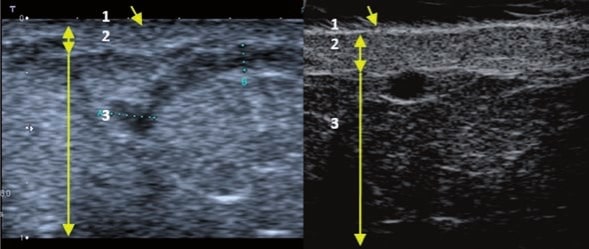

Die Doppler-Sonographie ermöglicht die Darstellung großer Gefäße und Perforatoren, die sich meist in tieferen Bereichen des subkutanen Gewebes befinden. Mit klassischem Ultraschall lassen sich kleinere Gefäße jedoch nicht darstellen. Für die Darstellung kleinerer Gefäße, die oberflächlich unter der Epidermis und im oberen subkutanen Gewebe liegen, wird HFU eingesetzt. Mit Sonden über 20 MHz Frequenz erhält man hochauflösende Ultraschallbilder, auf denen Objekte kleiner als 0,1 mm unterscheidbar sind. Mit zunehmender Auflösung nimmt jedoch die Eindringtiefe ab. Je nach Sonde und Gerät beträgt die maximale Eindringtiefe etwa 20–30 mm. Diese Eindringtiefe bei gleichzeitig hoher Bildauflösung ermöglicht die Beurteilung sehr kleiner Gefäße. HFU erlaubt die genaue Bestimmung des Verlaufs und der Lage kleiner Gefäße in der Haut, was entscheidend für die Wahl der Verschlussmethode und die Planung des Eingriffs ist. Oft sind an der Hautoberfläche nur wenige Gefäße sichtbar – erst durch die Ultraschalluntersuchung lässt sich die tatsächliche Anzahl und der Verlauf feststellen. Für einen erfolgreichen Verschluss muss das gesamte Gefäß behandelt werden, nicht nur der sichtbare Teil, da sonst eine schnelle Rekanalisation erfolgt (7). Häufig ändert das an der Haut sichtbare Gefäß seinen Verlauf, wird gewundener und zieht in tiefere Hautschichten (8). HFU ermöglicht zudem die Darstellung der Perforatoren zwischen kleinen Gefäßen und die Messung grundlegender Parameter wie Durchmesser, Wandstärke, Tiefe und Blutfluss (6). Mit der 40-MHz-Sonde von Ultrasonix kann auch der Blutfluss mittels Farbdoppler visualisiert werden.

Transkutane Laserbehandlungen zum Verschluss von Gefäßen gewinnen an Popularität. Dabei wird Lichtenergie von Hämoglobin in den Erythrozyten absorbiert und in Wärme umgewandelt, was die Gefäßwand koaguliert. Bei kleinen Teleangiektasien ist der Effekt sofort sichtbar, bei retikulären Venen erfolgt der Verschluss erst Wochen nach dem Eingriff (9). Der Erfolg hängt von den gewählten Parametern ab. Die genaue Bestimmung der Gefäßtiefe und des Durchmessers ist entscheidend. HFU ermöglicht präzise Messungen, auf deren Grundlage Laserart, Wellenlänge, Impulsdauer, Spotgröße und Energiedichte festgelegt werden (7). HFU dient auch der Überwachung der Korrektheit und Wirksamkeit des Eingriffs.

Sklerotherapie verschließt Gefäße durch Injektion eines chemischen Obliterans. Sie ist kostengünstig und relativ einfach durchzuführen. Hauptsächlich für retikuläre Venen >3 mm, kann aber auch bei kleineren Gefäßen eingesetzt werden (10). Bei Gefäßen <3 mm ist die Punktion schwierig, wodurch Komplikationen wahrscheinlicher werden (7). HFU hilft hier, den Gefäßverlauf exakt darzustellen und den Eingriff unter Ultraschallkontrolle durchzuführen, wodurch das Risiko einer Nekrose durch Fehlinjektion minimiert wird. HFU überwacht zudem die Wirksamkeit des Eingriffs.